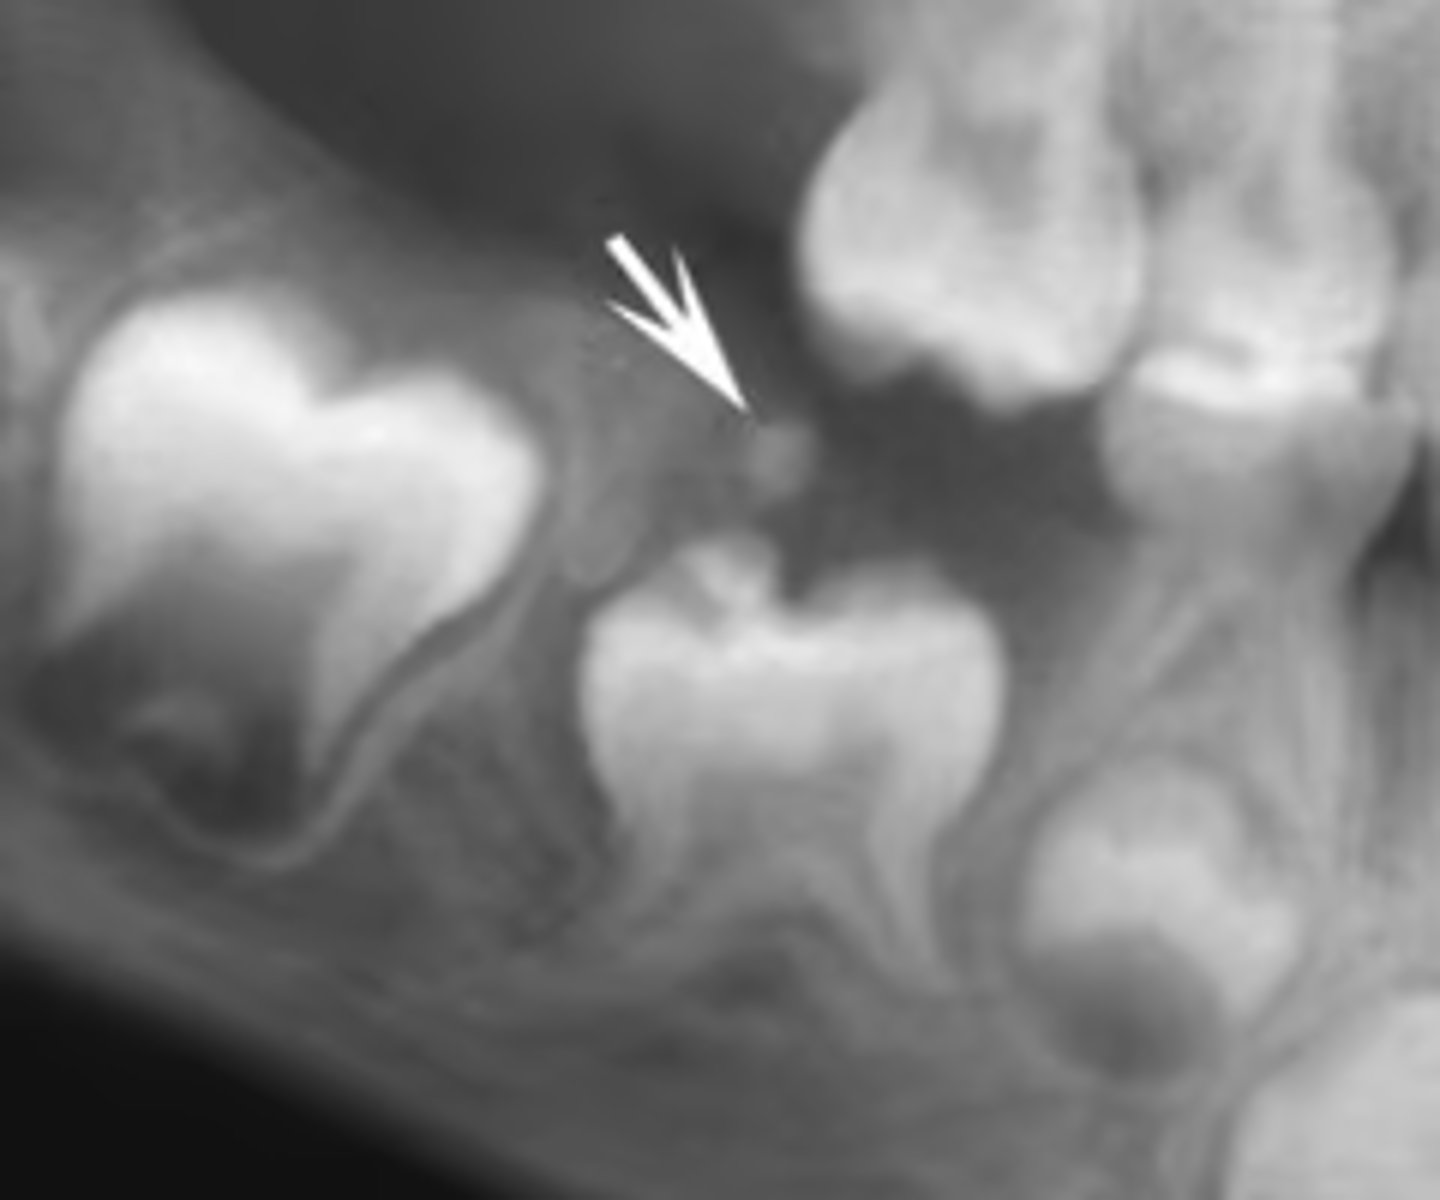

How would you describe the lesion?

- Periapical radiolucency associated with #30

- Has a band of sclerotic change extending from the apical radiolucency to the inferior alveolar canal and beyond

- Furcation involvement

(Furcation involvement as well as a band of sclerotic change extending from the apical radiolucency to the inferior alveolar canal and beyond)

What category would you put this lesion into?

Inflammation

what could be a differential diagnosis for this lesion? (select all that apply)

A. PCOD

B. multiple myeloma

C. apical rarefying osteitis

D. chronic sclerosing osteomyelitis

Also note apical rarefying osteitis #14 ( remnant root fragments, no crown due to caries)